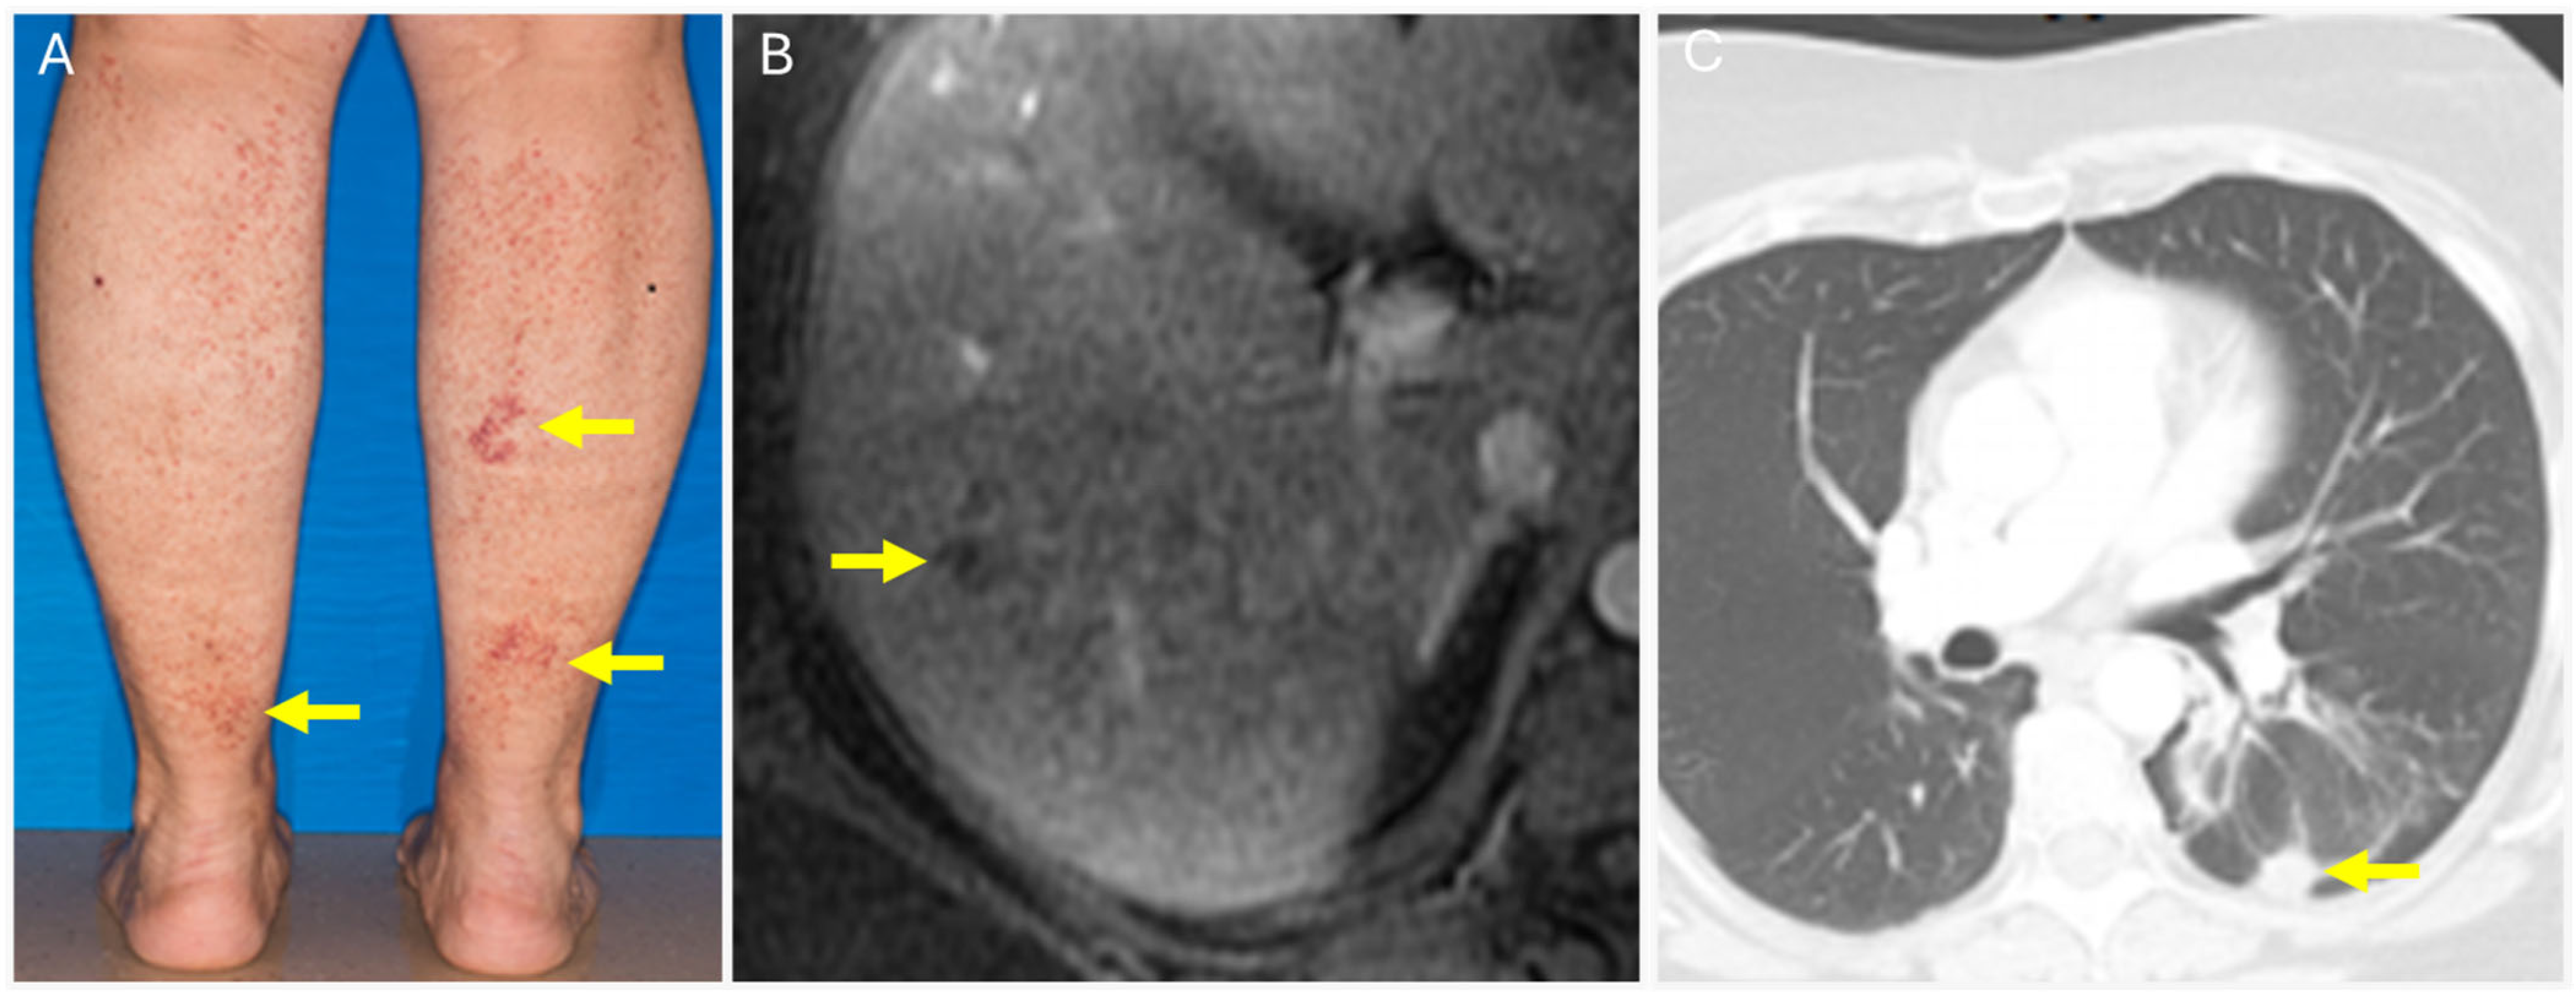

5. Cutaneous Manifestations of Monoclonal Gammopathy of Clinical Significance (MGCS)

5.1. Type 1 Cryoglobulinemia

| Monoclonal gammopathy of cutaneous significance |

|